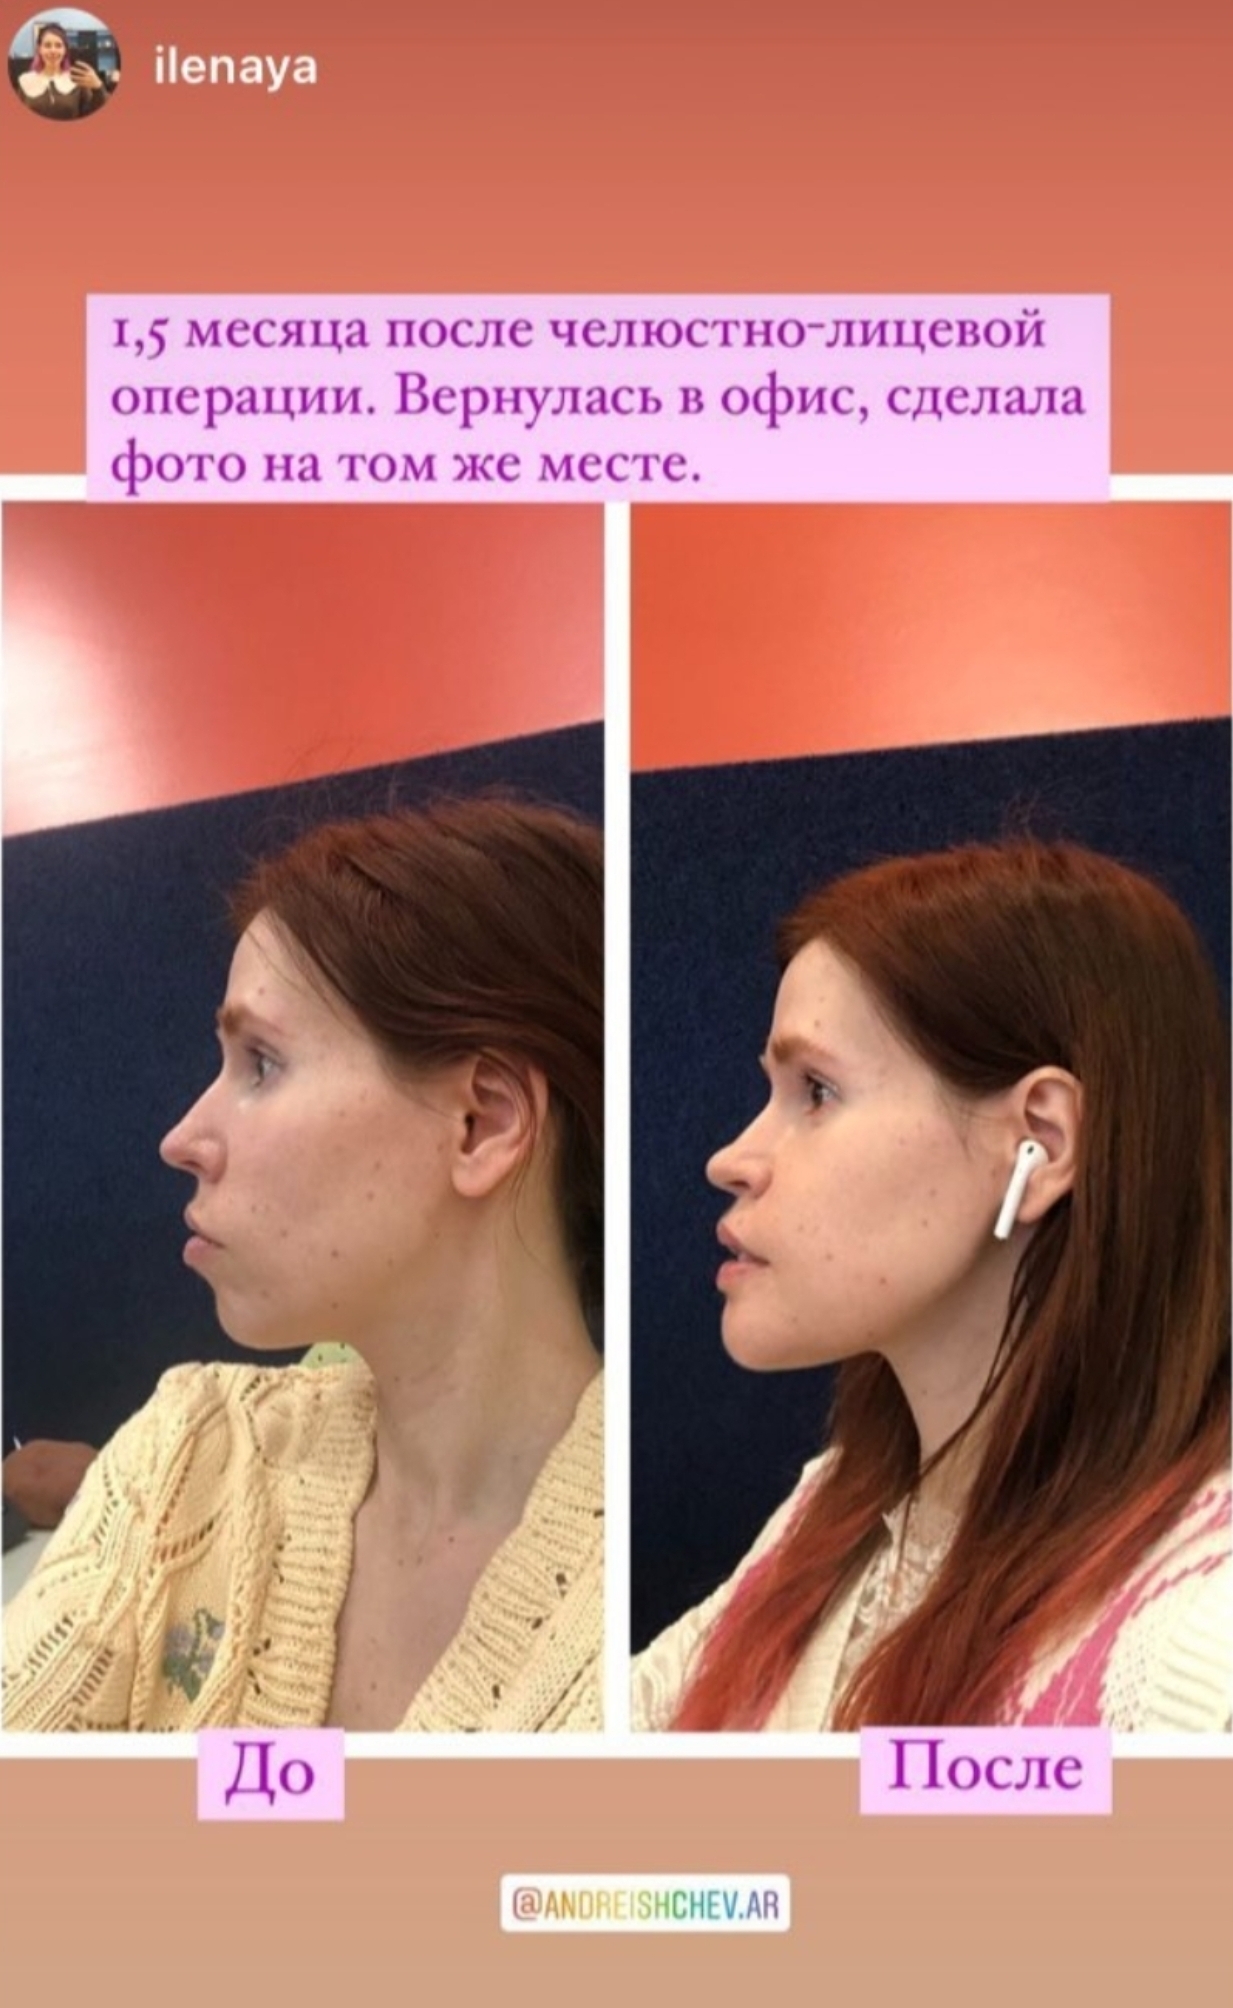

I'm planning to get a jaw surgery, lefort 1 downgrafting in Russia. I live in Georgia but this is a dream of mine to be able to finally smile properly. Surgeons in Georgia suck so I'm traveling to Russia since its cheaper than turkey and i think better.

if you could recommend me surgeon in Russia, I'd be very grateful. I found 2 good ones andreishchev who is responsive and Kurakin who ignored me on instagram but i joined their telegram channel